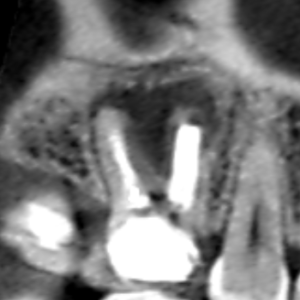

上顎大臼歯の近心頬側根の冠状断のCT画像です。

矢印の先に近心頬側根をとり巻くように大きな膿の影がみられます。

歯根破折を疑わせる画像です。